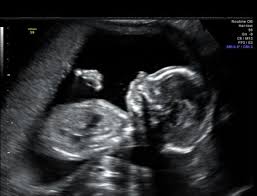

Certain features detected during a second trimester ultrasound exam are potential markers for Downs syndrome and they include dilated brain ventricles absent or small nose bone increased. But there is nothing to worry about and my child is perfectly normal Becauese my first-trimester scan and blood test were both normalBUT I need to make an appointment with a genetic. Approximately 30 of babies with Down syndrome have detectable abnormalities on the mid-trimester ultrasound 1.

One was a cyst in the babies brain. Apparently these can be indicators that your baby has down syndrome.

Finding Down Syndrome Via Ultrasound Little Doctors